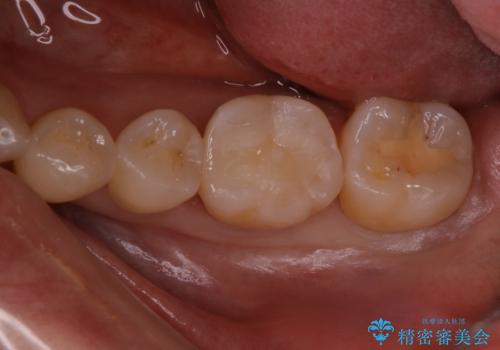

- 検査の結果、虫歯が見つかった患者様です。

白く目立たないものでの治療をご希望されたため、セラミックインレーでの治療となりました。

適合の良いセラミックインレーで修復することで見た目の綺麗さを保ったまま治療することができます。